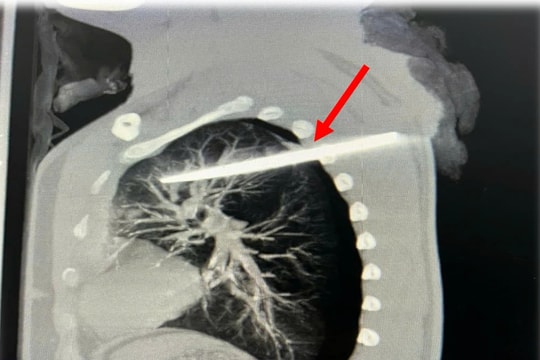

Cấp cứu kịp thời người đàn ông nguy kịch do vết thương thấu ngực, kèm dị vật sâu trong phổi

Bệnh viện Trung ương Quân đội 108 tiếp nhận và điều trị trường hợp nam bệnh nhân D.T.Đ (29 tuổi, Hà Nội) nhập viện trong tình trạng nguy kịch do vết thương thấu ngực nghiêm trọng, kèm theo dị vật cắm sâu trong phổi.